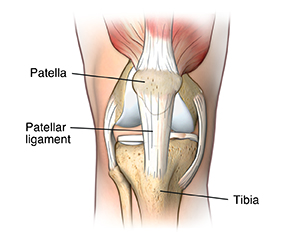

Jumper's knee, also known as patellar tendonitis, is a condition characterized by inflammation of your patellar tendon (or patellar ligament). This connects your kneecap (patella) to your shinbone (tibia). Jumper’s knee weakens your tendon, and, if untreated, can lead to tears in your tendon.

Jumper’s knee is inflammation of your patellar tendon, the tendon that connects your kneecap (patella) to your shinbone (tibia).